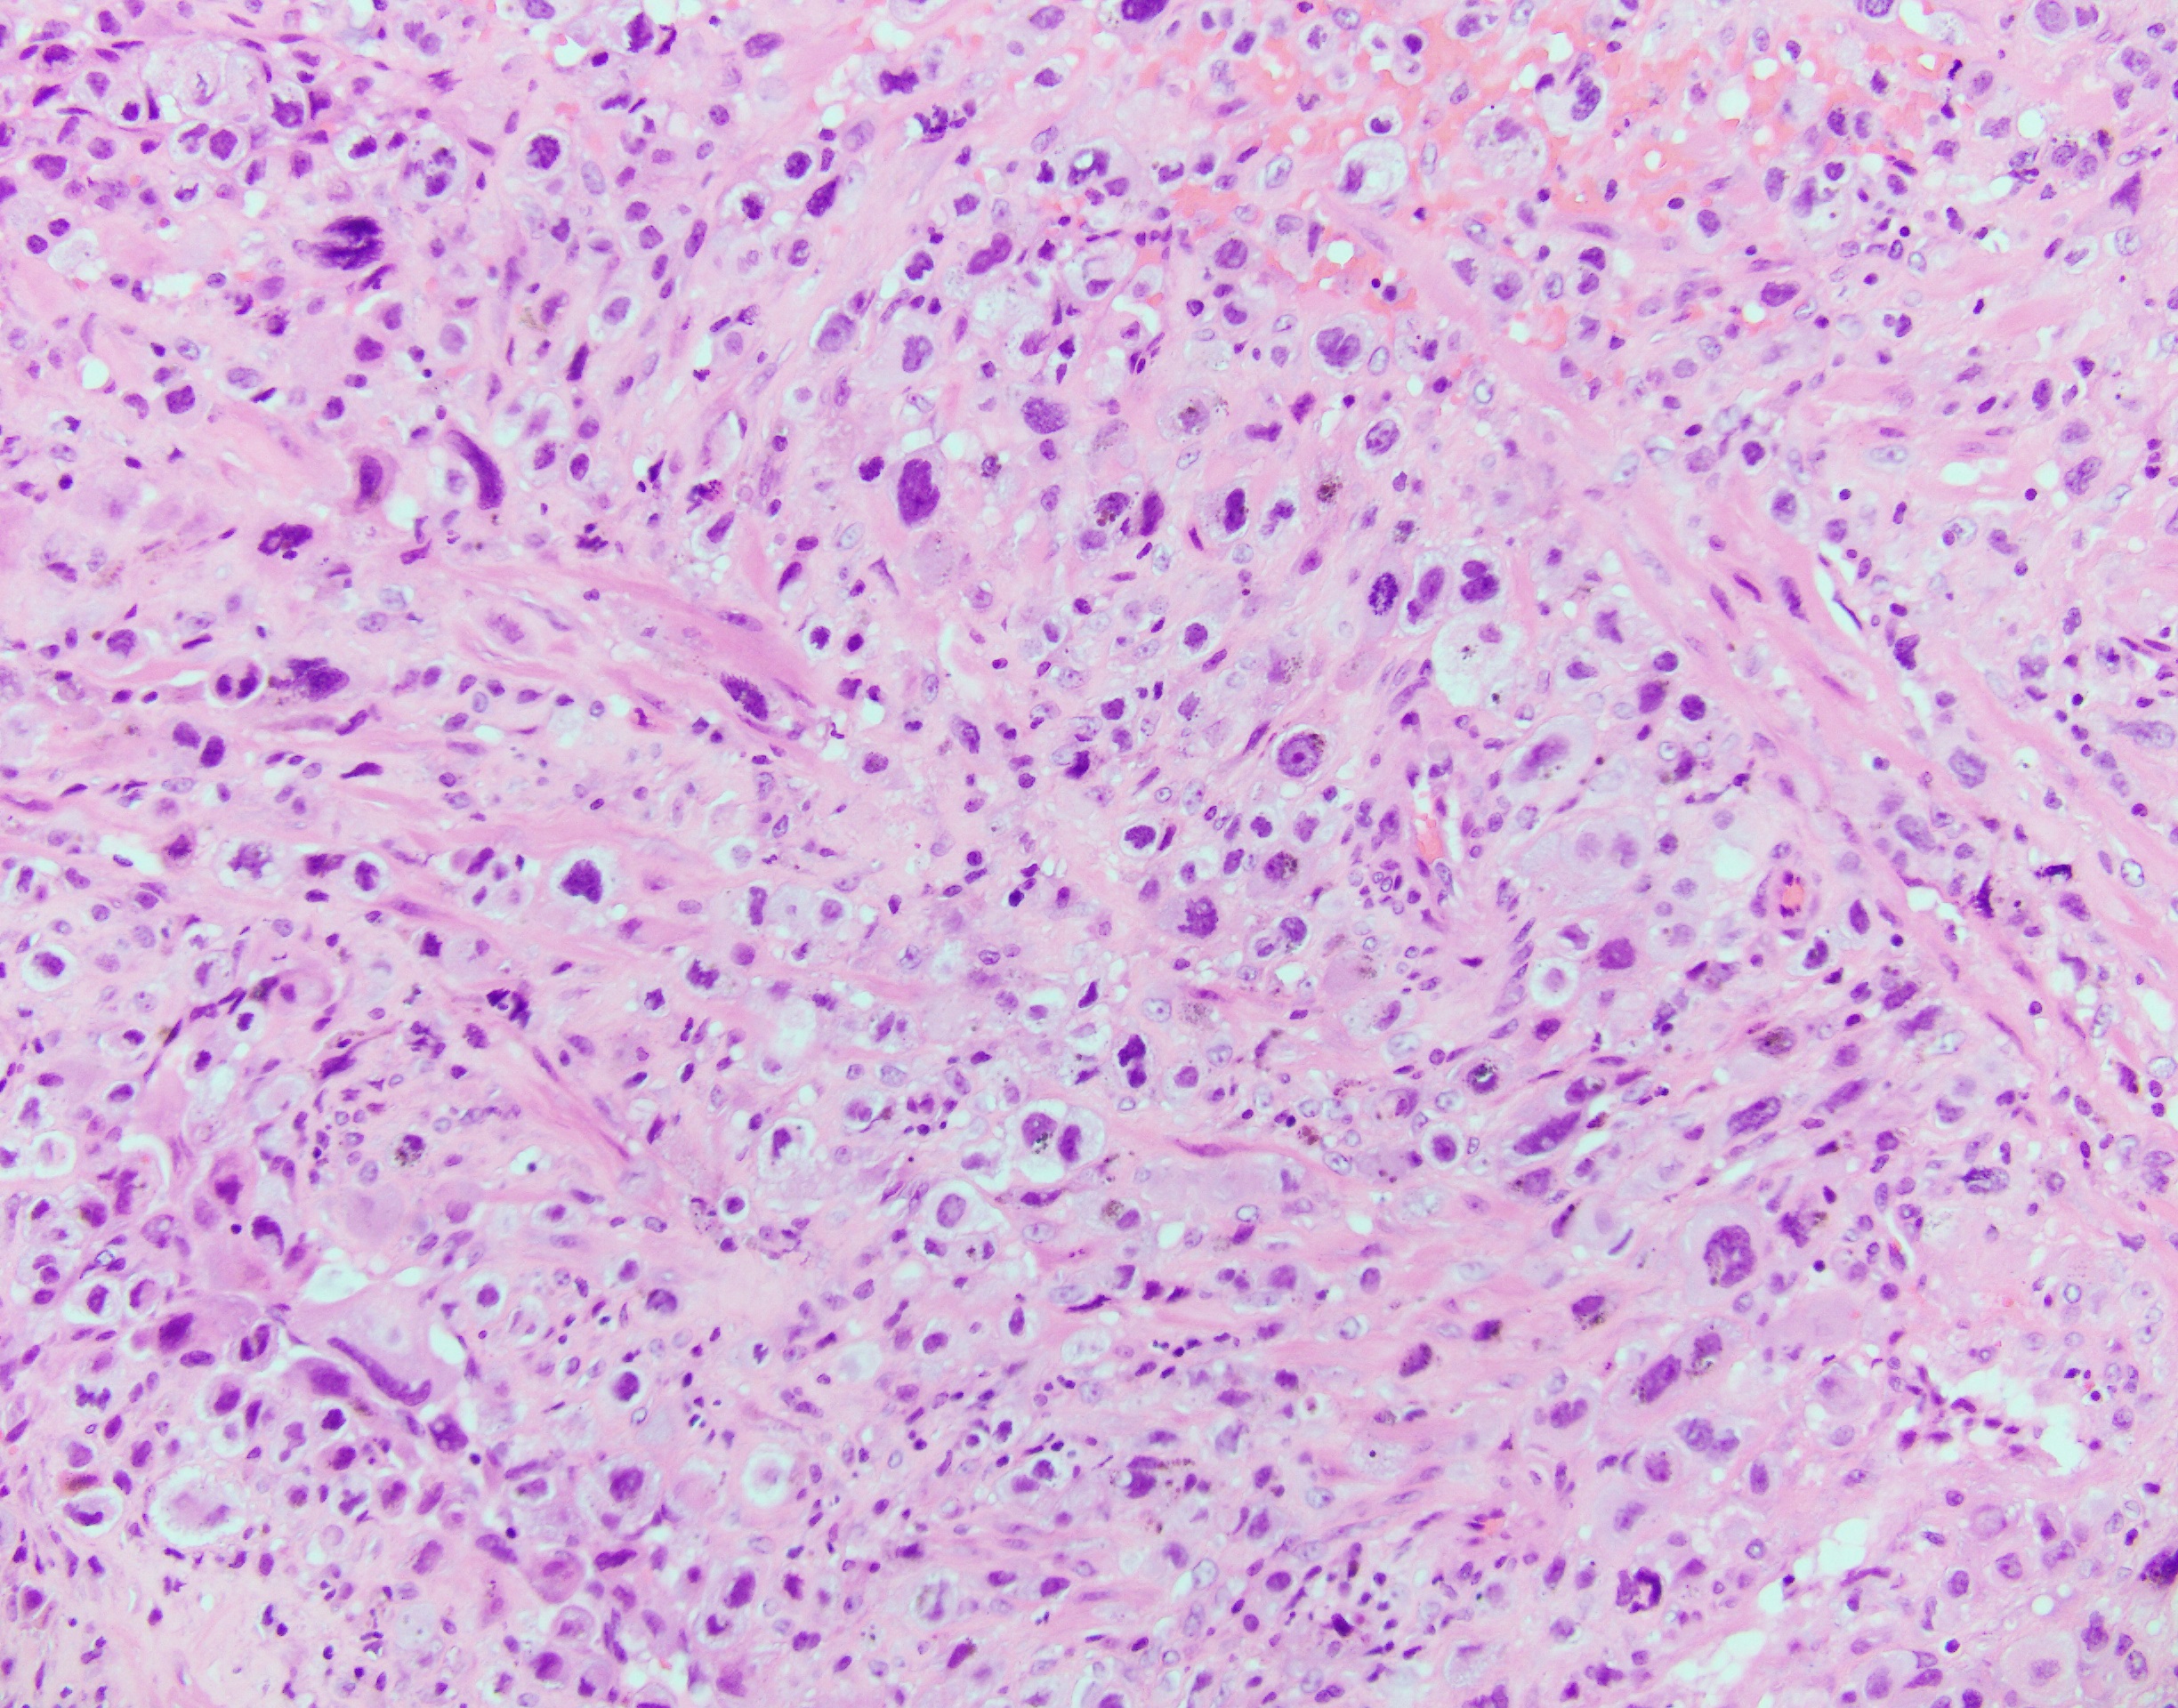

Histologically, the tumor has an infiltrative growth pattern consisting of aggregates or sheets of large, polyhedral to round, predominantly mononucleated cells, with scattered multinucleated cells. The tumor typically infiltrate the myometrium by separating the smooth muscle cells. The cells usually have abundant amphophilic and occasionally eosinophilic or clear cytoplasm. Nuclei are pleomorphic with atypia, large, convoluted and marked hyperchromasia. Most tumors have low mitotic activity. Charactaristic vascular invasion is often present, where tumor cells replace the vessel wall of myometrial vessel.

Top differential diagnosis include exaggerated placental site (EPS), epithelioid trophoblastic tumor (ETT) and gestational choriocarcinoma. EPS would show Ki67 proliferation index 1-5%. ETT has similar histologic features on H&E but stains diffuse positive for p63. Gestational choriocarcinoma would show a Ki67 proliferation index >90%.